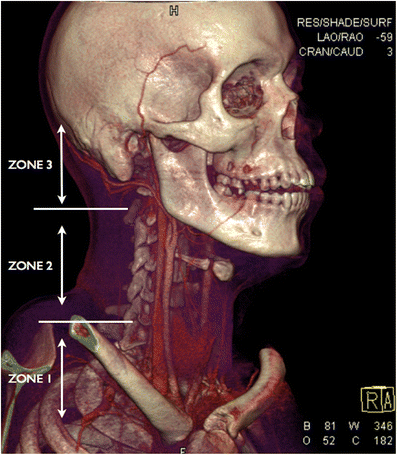

Location and classification

Three-dimensional volume rendering technique (3D VRT) of MDCTA performed on a young male victim of a stab wound to the neck demonstrating the anatomical trauma zones in penetrating injury of the neck. In this young patient, the cricoid cartilage has not yet calcified and therefore is not visualised on the VRT but the thyroid gland is visible (the lower border of the cricoid cartilage will be located just above the level of the isthmus of the thyroid gland)